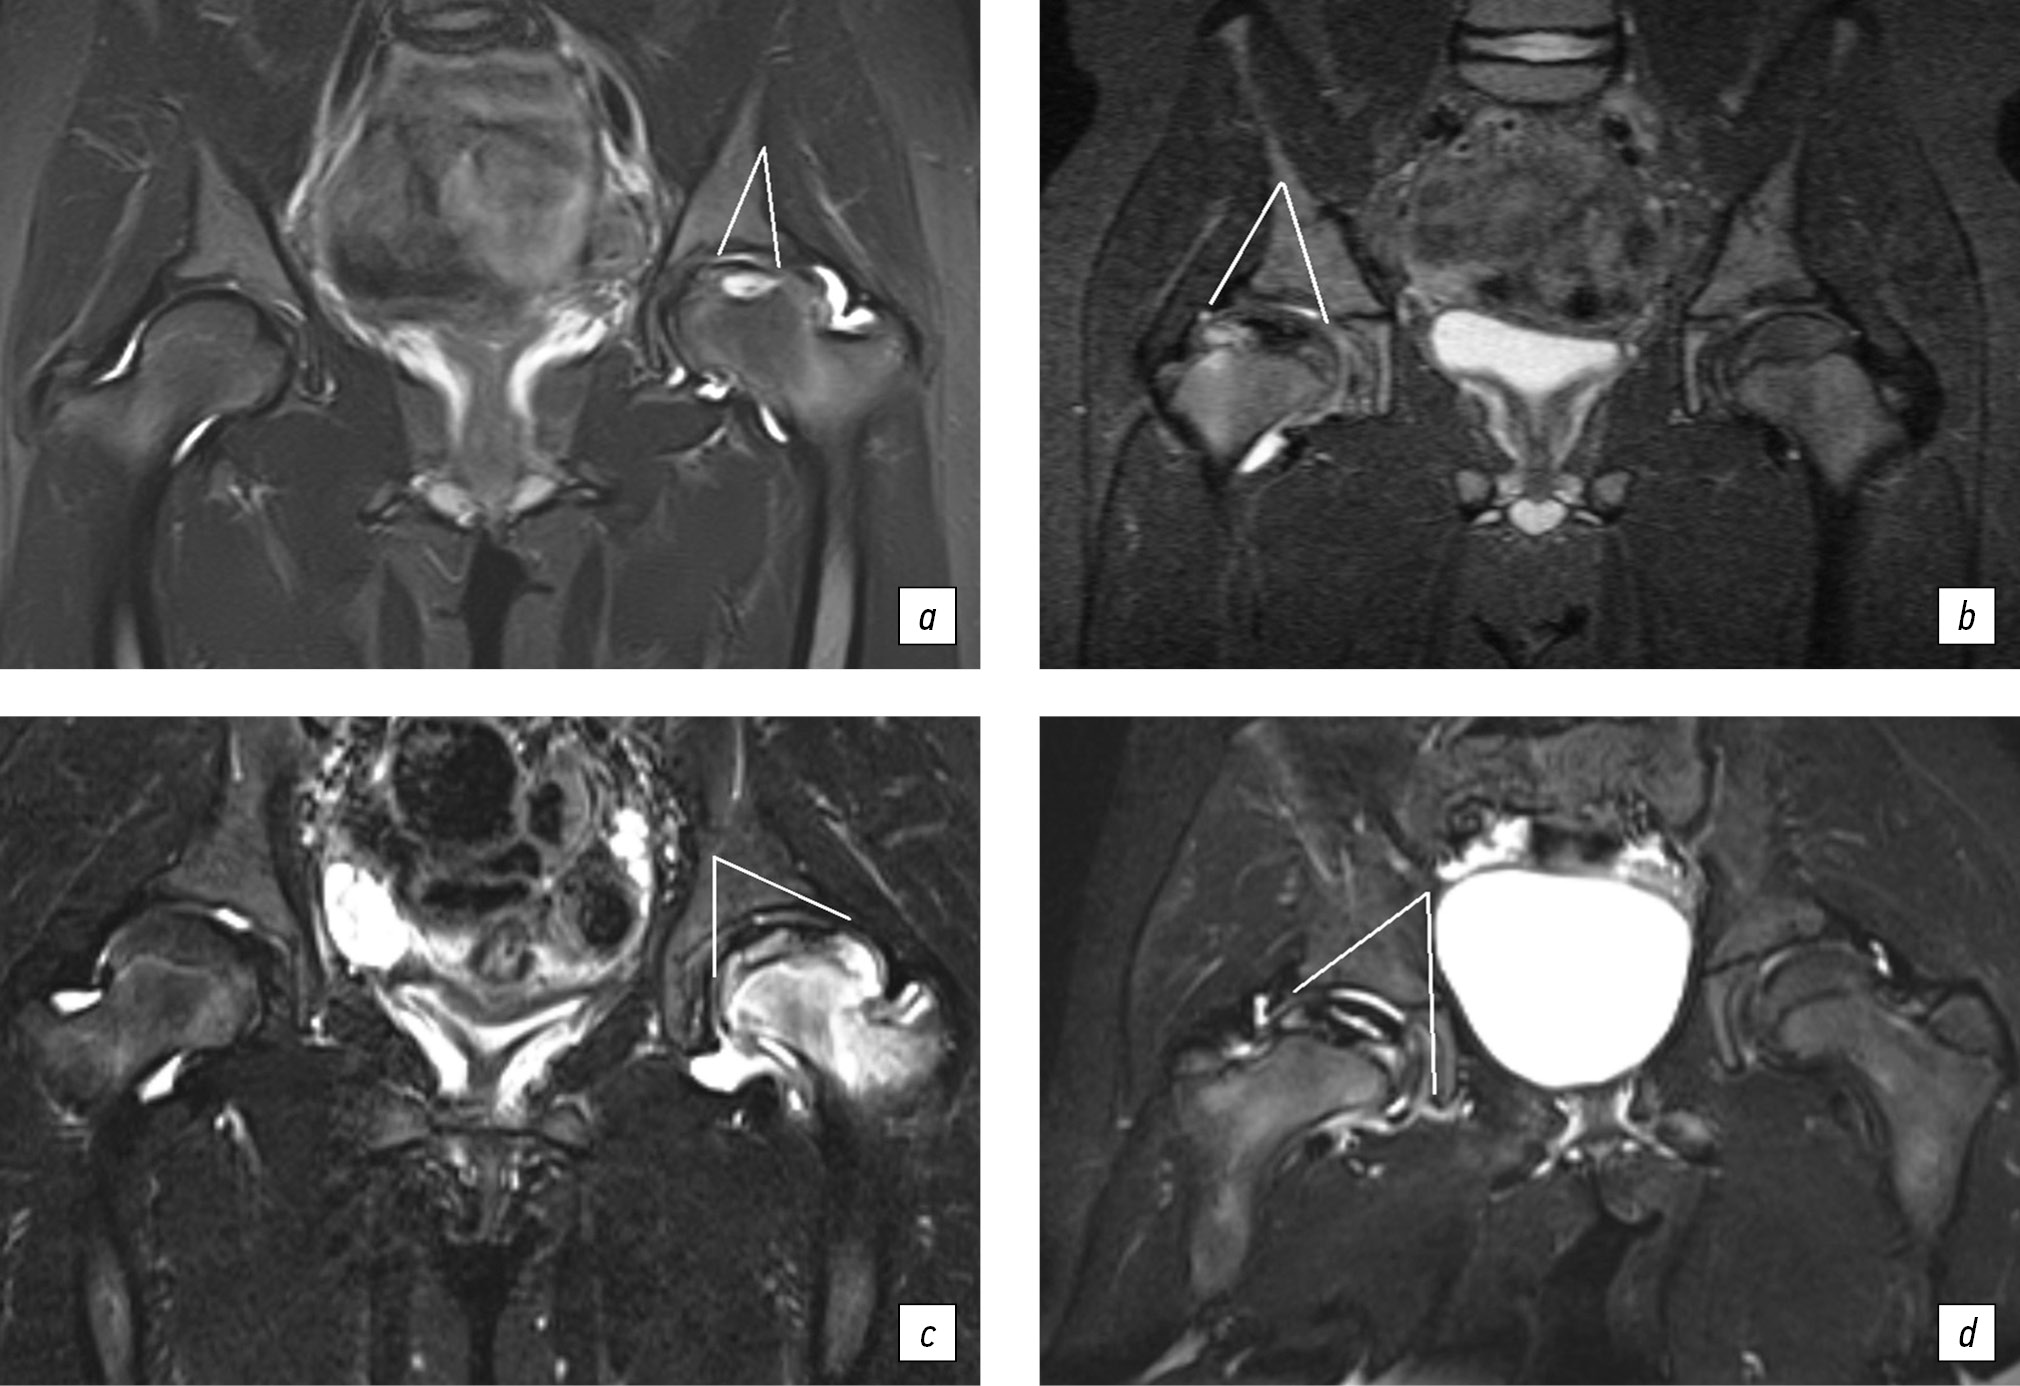

Для оценки воспаления тазобедренного сустава по шкале SCORING OF HIP MRI FOR JIA определяли степень утолщения синовиальной оболочки и наличие выпота. Измерения проводили на T2 STIR в коронарной плоскости два рентгенолога. При подсчете МР-признаков воспаления использовали градацию от 0 до 3, где 0 — отсутствие выпота и утолщения синовиальной оболочки; 1 — минимальное скопление выпота в капсуле сустава; 2 — умеренное скопление синовиальной жидкости с растяжением капсулы сустава и реакцией синовиальной оболочки; 3 — значительное скопление синовиальной жидкости с растяжением капсулы сустава и пролиферацией синовиальной оболочки (рис. 2).

Рис. 2. Магнитно-резонансная томограмма: признаки различной степени выраженности синовита тазобедренного сустава у детей с болезнью Легга – Кальве – Пертеса. В режимах STIR представлены: минимальное скопление выпота в капсуле сустава (а); умеренное скопление синовиальной жидкости с растяжением капсулы сустава и реакцией синовиальной оболочки (б, в); значительное скопление синовиальной жидкости с растяжением капсулы сустава и пролиферацией синовиальной оболочки (г)

Тяжесть поражения головки бедренной кости оценивали по объему очага некроза и интенсивности трабекулярного отека прилежащих отделов костной ткани и выражали в балах, где 0 — отсутствие очага некроза и трабекулярного отека; 1 — объем очага некроза и зона трабекулярного отека занимают не более 33 % эпифиза; 2 — объем очага некроза и зона отека занимают 34–66 % эпифиза; 3 — объем очага некроза и зона отека занимают 67–100 % эпифиза (рис. 3). Таким образом, максимальное суммарное число балов — 6. Считалось, что остеоартрит с высокой степенью активности соответствует 5–6 баллам, умеренной активности — 3–4 баллам, низкой активностью — 2 баллам. Неактивная стадия остеоартрита у детей соответствует 0–1 баллу при условии отсутствия очага некроза (рис. 4). Лабораторный комплекс включал определение значений стандартных маркеров воспалительной активности и костного метаболизма, а также уровень кальпротектина, виментина, интерлейкина-6 (IL6), фактора некроза опухоли альфа (TNF-α) в сыворотке крови, титра антинуклеарного фактора (АНФ) на клеточной линии HEp-2 на момент верификации остеоартрита. Всем детям также проводили тестирование на наличие антифосфолипидного синдрома и гипергомоцистеинемии.

Рис. 3. Магнитно-резонансная томограмма: признаки различной тяжести поражения головки бедренной кости у детей с болезнью Легга – Кальве – Пертеса. На магнитно-резонансной томограмме в режимах STIR представлены: объем очага некроза и зона трабекулярного отека занимают не более 33 % эпифиза (а); объем очага некроза и зона отека занимают 34–66 % эпифиза (б); объем очага некроза и зона отека занимают 67–100 % эпифиза (в, г)